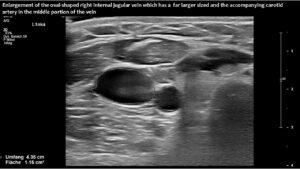

However, in this patient, both jugular veins were compressed. The middle portion of the internal jugular vein was pushed ventrally by the increased cervical lordosis on both sides, becoming squeezed between the carotid artery and the sternocleidomastoid muscle.

Consequently, blood had difficulty leaving the skull, resulting in continuously increased pressure and severe headaches, as well as other neurological dysfunction. The left side was more affected due to the double compression. This was clearly demonstrated by four-dimensional volume flow measurements in both jugular veins.